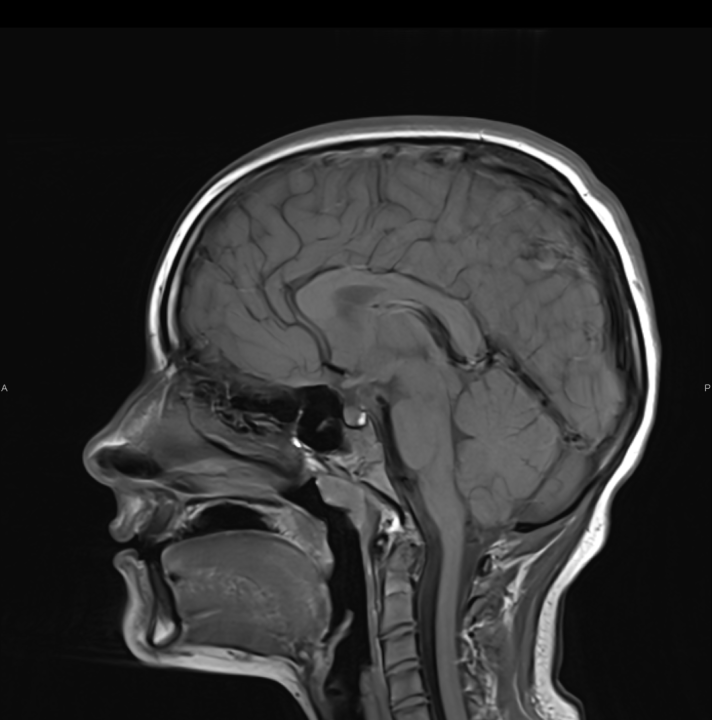

FOTO Ako su vam potrebni specijalistički pregledi mamografija, RTG, UZV, CT i MR, koji se inače koriste za dijagnostiku velikog broja zdravstvenih problema, možete ih obaviti već danas ili sutra. Vodite računa o vašem zdravlju i zakažite pregled u Poliklinici Affidea Vita u Šibeniku na vrijeme!